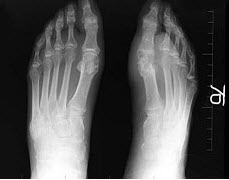

28、单项选择题

女,根据其正常足的影像图像,判断其最可能的年龄()

A.52岁左右

B.42岁左右

C.12岁左右

D.22岁左右

E.32岁左右

点击查看答案